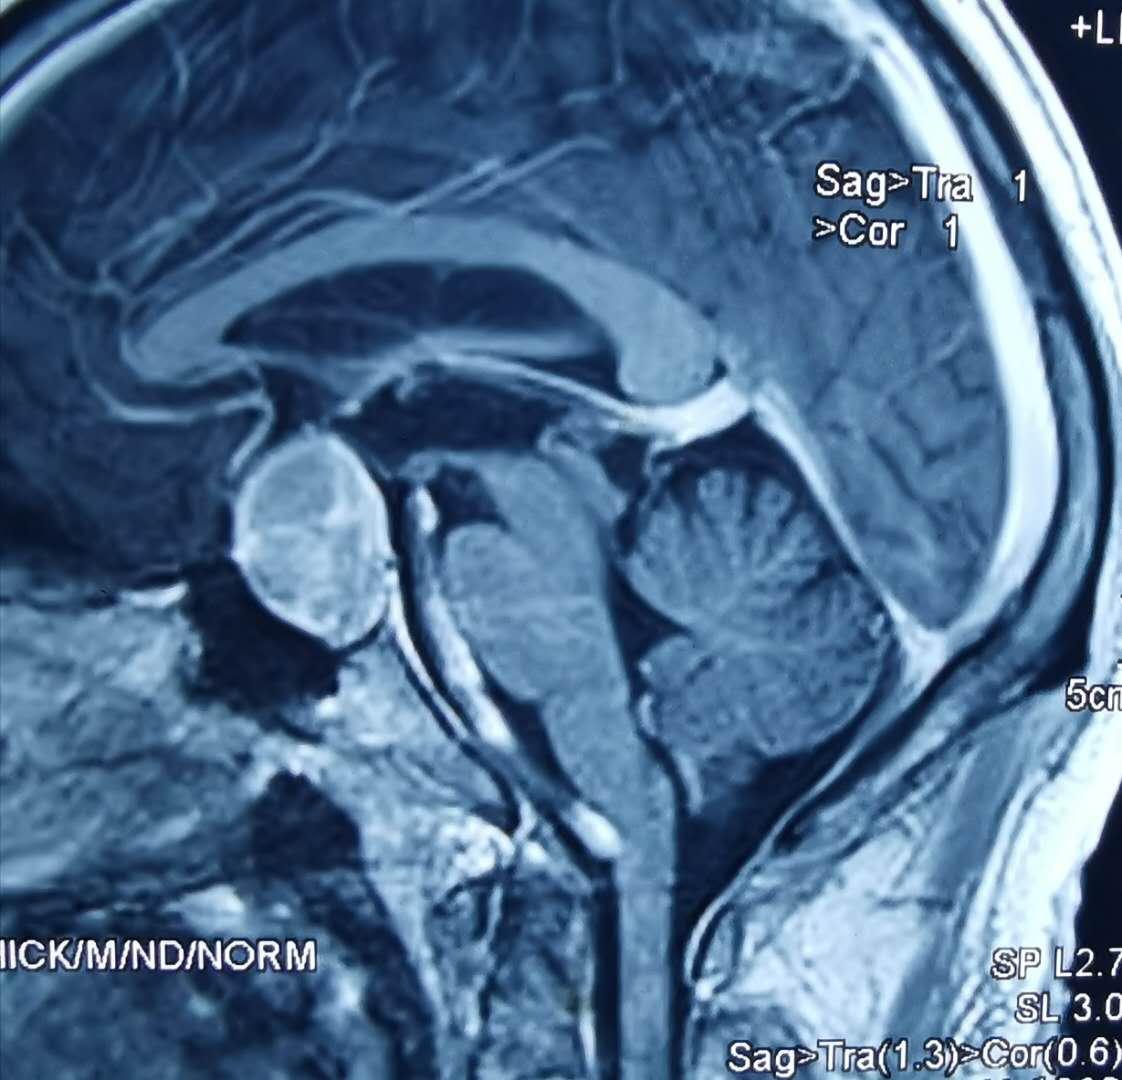

对于泌乳素明显增高,尤其是大于150的患者,应考虑垂体泌乳素腺瘤可能,应该行垂体的薄层核磁共振增强扫描,一般可以确诊。

核磁共振扫描